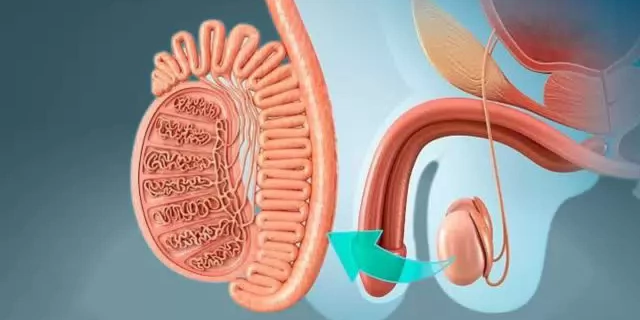

Echografie Scrotum voor Huisartsen

Leer tijdens deze eendaagse cursus hoe je testisproblematiek en afwijkingen effectief diagnosticeert.